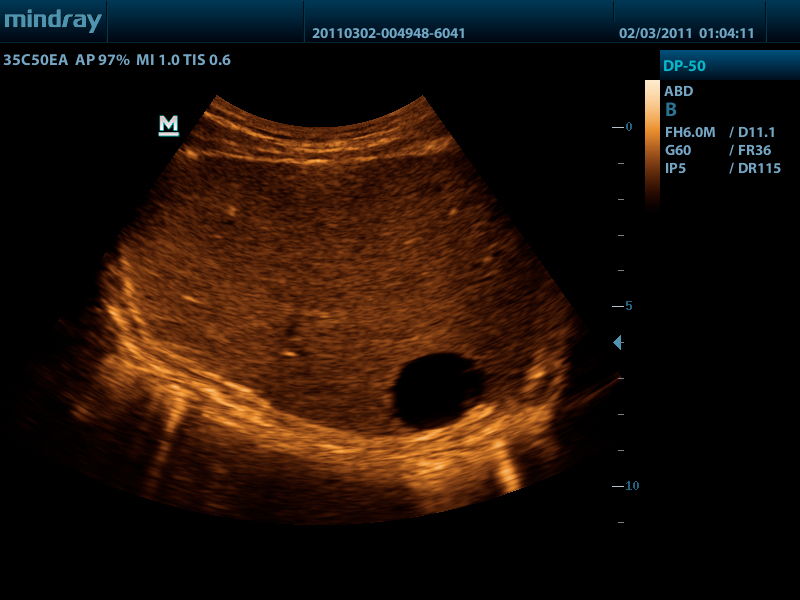

Портативный ультразвуковой сканер Mindray DP-50

Mindray DP-50 – портативная цифровая ультразвуковая система с ЖК монитором 15 дюймов (1024Х768)

и встроенными аккумуляторными батареями (опция) позволяющими работать в автономном режиме до 2-х часов.

Достоинства Mindray DP-50:

- карты колоризации (псевдоокрашивание).

DP-50 – портативный УЗИ сканер разработан на базе новой платформы X-treme engine, используемой в хорошо зарекомендовавших себя цветных сканерах с доплером моделей DC-3, DC-7, DC-6. Эта платформа открывает возможности для расширений до уровня цветных сканеров и совместимости с широким диапазоном периферийного оборудования. X-treme означает интеллект, высокую скорость обработки данных, многоуровневую передачу сигналов, а также возможность оптимизации изображения и модульного расширения.

Качество изображения:

- iBeam: функция улучшения разрешающей способности изображения

- iClear: функция подавления шумов на изображении для улучшения детализации и контрастности изображения

- изображение на основе гармоник с фазовым сдвигом

- трапецевидное изображение, псевдоокрашивание и B Steer

Применяемые датчики DP-50:

Конвексный датчик 35C50EA (2.0/3.5/4.5/5.0/Н5.0/Н6.0) R50